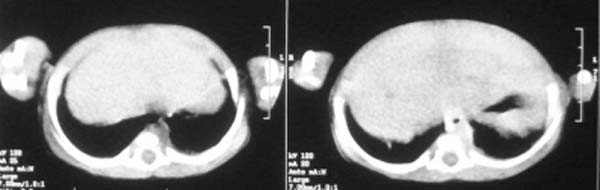

这个病例定位诊断:1、可以肯定肿块不在肝脏。2、肿块在腹膜后,因为肠管向前侧方推移,肾脏明显向后推挤,腹主动脉及下腔静脉被肿块包绕。

我的意见是-----定位诊断是“1、可以肯定肿块不在肝脏。2、肿块在腹膜后,因为肠管向前侧方推移,肾脏明显向后推挤,腹主动脉及下腔静脉被肿块包绕。”

右中下腹部囊实性密度影,内有小细条状钙化影,胃及腹部肠管受压向左移位,肾脏受压向后移位,腹主动脉及下腔静脉包饶。考虑腹膜后畸胎瘤可能性大。